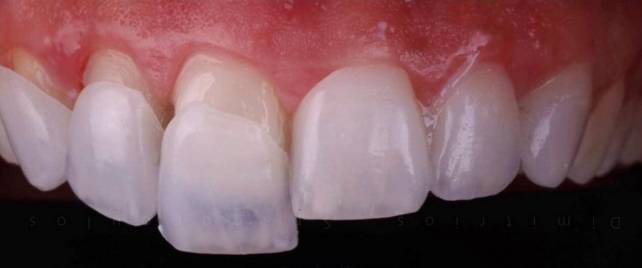

To prepare a tooth for porcelain veneers, a small amount of enamel is removed. As a result, the tooth will have a slightly thinner surface, which will increase the likelihood that the veneer will stay in place for years. The veneer is made to match the shade of your natural teeth, so it should blend in well. The porcelain veneer is bonded to the surface of the tooth with dental cement. Veneers are extremely durable, and with proper dental care, they can last anywhere from 10 to 15 years.